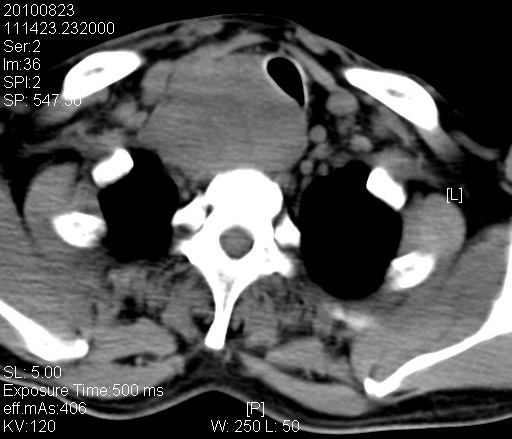

三个疗程结束后患者呼吸困难(一个疗程后),饮食呛咳(两个疗程后)好转,但仍有声音嘶哑。颈部肿块消失,颈部彩超提示可见1.6*1.4cm,1.5*1.0cm的肿大淋巴结。颈胸腹CT:右锁骨上及前纵隔见肿大淋巴结影,气管稍受压,最大经约2.0cm(治疗前6.5cm)。后腹膜见多枚肿大淋巴结,最大经约0.6cm(治疗前2.0cm).

化疗后